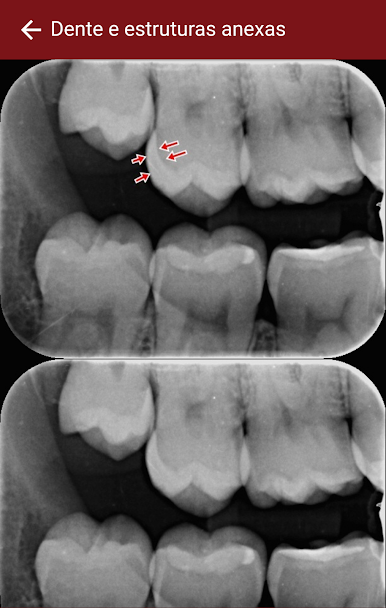

RadioXtudy feels like a focused helper for anyone learning how to read dental X‑rays. The layout is simple and direct, so nothing gets in the way. Topics are split into clear sections like Anatomy, Pathology, and Dental anomalies, which makes it easy to jump right to what someone needs to review. It aims to teach, not to show off, and that gives it a calm, classroom kind of pace. Notes are short, examples are to the point, and there are exercises that help lock the material in after each topic.

There is a small community area where users can trade questions or compare thoughts, so it does not feel like studying alone all the time. Running it on a PC with BlueStacks is nice because the images are larger, zooming on details is easier, and it is simple to keep a PDF or lecture slides open on the side. It is clearly meant for graduate dentistry students and dental surgeons, but anyone brushing up for clinic or prepping for exams would get value from it. There are no flashy extras or game-y bits, just practical steps toward better radiographic interpretation. Someone who wants fast entertainment will not find that here, but for steady learning in dental radiology, it does what it says and stays out of the way.